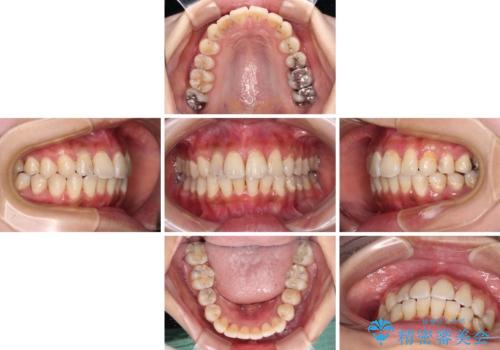

デコボコで磨きにくい前歯をスッキリと インビザライン矯正

- 虫歯が多く、磨きにくい歯並びを改善したいとのことで来院された患者様です。

歯列は叢生が認められる程度でしたが、やや前突感があったので、少しでも口が閉じやすくなるように仕上げる方針としました。

神経を取り除かれている歯3本以外にも虫歯が認められたため、事前に処置を行い、インビザラインにて矯正治療を行うこととしました。

神経が取り除かれている歯は、クラウンによる補綴治療が必要であるため、矯正治療後にオールセラミッククラウンにて補綴治療を行うこととしました。

歯磨きしやすくなるとともに、飛び出していた前歯も引っ込めて整えることができました。